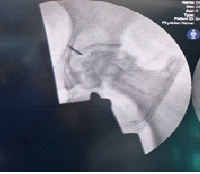

A 30-year-old primigravida at 38 weeks +4 days of gestation presented to the emergency department after a road traffic accident involving a four-wheeler collision. She reported pain and deformity in the left upper limb. The patient had no prior medical comorbidities, and her pregnancy had progressed uneventfully following spontaneous conception. She had adhered to routine antenatal care, including regular intake of iron and calcium supplements, two doses of tetanus vaccination, and standard antenatal screening. She was blood group O-positive and tested negative for Group B Streptococcus. Her menstrual history was unremarkable, with regular cycles occurring every 28–30 days, lasting 3–4 days with average flow. On presentation, the patient was alert, oriented, and hemodynamically stable (blood pressure 100/70 mmHg, heart rate [HR] 98 bpm, RR 18/min, and SpO2 99% on room air via left upper limb). She was afebrile, with no pallor or pedal edema. There was no history of loss of consciousness, ear, nose, throat bleeding, vomiting, or seizures. Local examination of the left upper limb revealed tenderness, swelling, and deformity without any open wounds. Motor and sensory functions were preserved, and radial and ulnar pulses were palpable. Abdominal examination revealed a uterine fundal height consistent with 36 weeks, a longitudinal lie, cephalic presentation, and a tense, rigid uterus. Irregular uterine contractions (2–3/10 min) were noted, along with reduced fetal movements. Cardiotocography (CTG) showed a baseline fetal HR of 175 bpm, with recurrent late decelerations and reduced beat-to-beat variability (<5 bpm). Doppler studies revealed increased umbilical artery resistance (pulsatility index [PI]: 1.48; S/D ratio: 4.2) and a decreased middle cerebral artery PI (PI: 0.82), resulting in a cerebroplacental ratio of 0.55 – indicative of a brain-sparing effect and consistent with intrauterine hypoxia. A non-stress ultrasound showed normal amniotic fluid volume and a singleton fetus in cephalic presentation with no placental or uterine abnormalities. The cervix was 2 cm dilated but closed. Routine laboratory investigations, including complete blood count, coagulation profile, and crossmatch, were within normal limits. Given the gestational age and maternal stability, a trauma protocol was activated involving obstetrics, orthopedics, anesthesiology, and neonatology teams. Plain radiographs of the right arm (with pelvic shielding) revealed a wedge-type diaphyseal fracture of the humerus (AO type 12B2). Closed reduction under traction was performed, and immobilization was achieved with an upper arm (U) slab(Figure 1). Given signs of fetal compromise – possibly due to placental abruption – the multidisciplinary team recommended conservative orthopedic management until delivery.

Figure 1: Pre-operative radiographs of left arm anteroposterior (a) and lateral (b) view showing a displaced distal 1/3rd shaft humerus fracture (AO type 12B2) with overriding fragments, and clinical images (c and d) showing limb immobilization in a U-slab in a third-trimester pregnant patient.